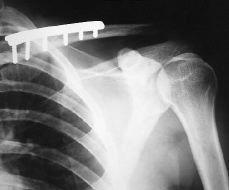

Paciente varón de 29 años de edad, sin antecedentes de interés, que sufre caída accidental con traumatismo directo sobre hombro izquierdo, presentando dolor e impotencia funcional en dicha articulación. A la exploración física se objetivó dolor y deformidad en hombro izquierdo con signo de la tecla positivo, sin déficit vasculonerviosos distales. En las radiografías realizadas (Fig. 1) se apreció una fractura de tercio medio de clavícula izquierda desplazada, asociada a luxación acromioclavicular tipo II de la clasificación de Tossy y cols.6,7 Fue intervenido quirúrgicamente, realizando reducción y fijación de la fractura de clavícula izquierda con placa DCP, así como revisión de los ligamentos acromioclaviculares, en los que se comprobó su integridad y fijación de la articulación acromioclavicular con dos agujas de Kirschner (Fig. 2). El paciente fue inmovilizado con sling, cursando el postoperatorio sin ningún incidente; las agujas se retiraron a las 4 semanas (Fig. 3) y tras un período de 3 años de seguimiento se observó una movilidad completa e indolora, alcanzando arcos articulares en el hombro afectado comparables al lado sano, así como unos resultados funcionales en los que se alcanzó una puntuación máxima en la escala de Constant2,25,20 (25/30) (Figs. 4 y 5).

Figura 2. Reducción de la fractura con placa y osteosíntesis con dos agujas de Kirschner de la luxación.